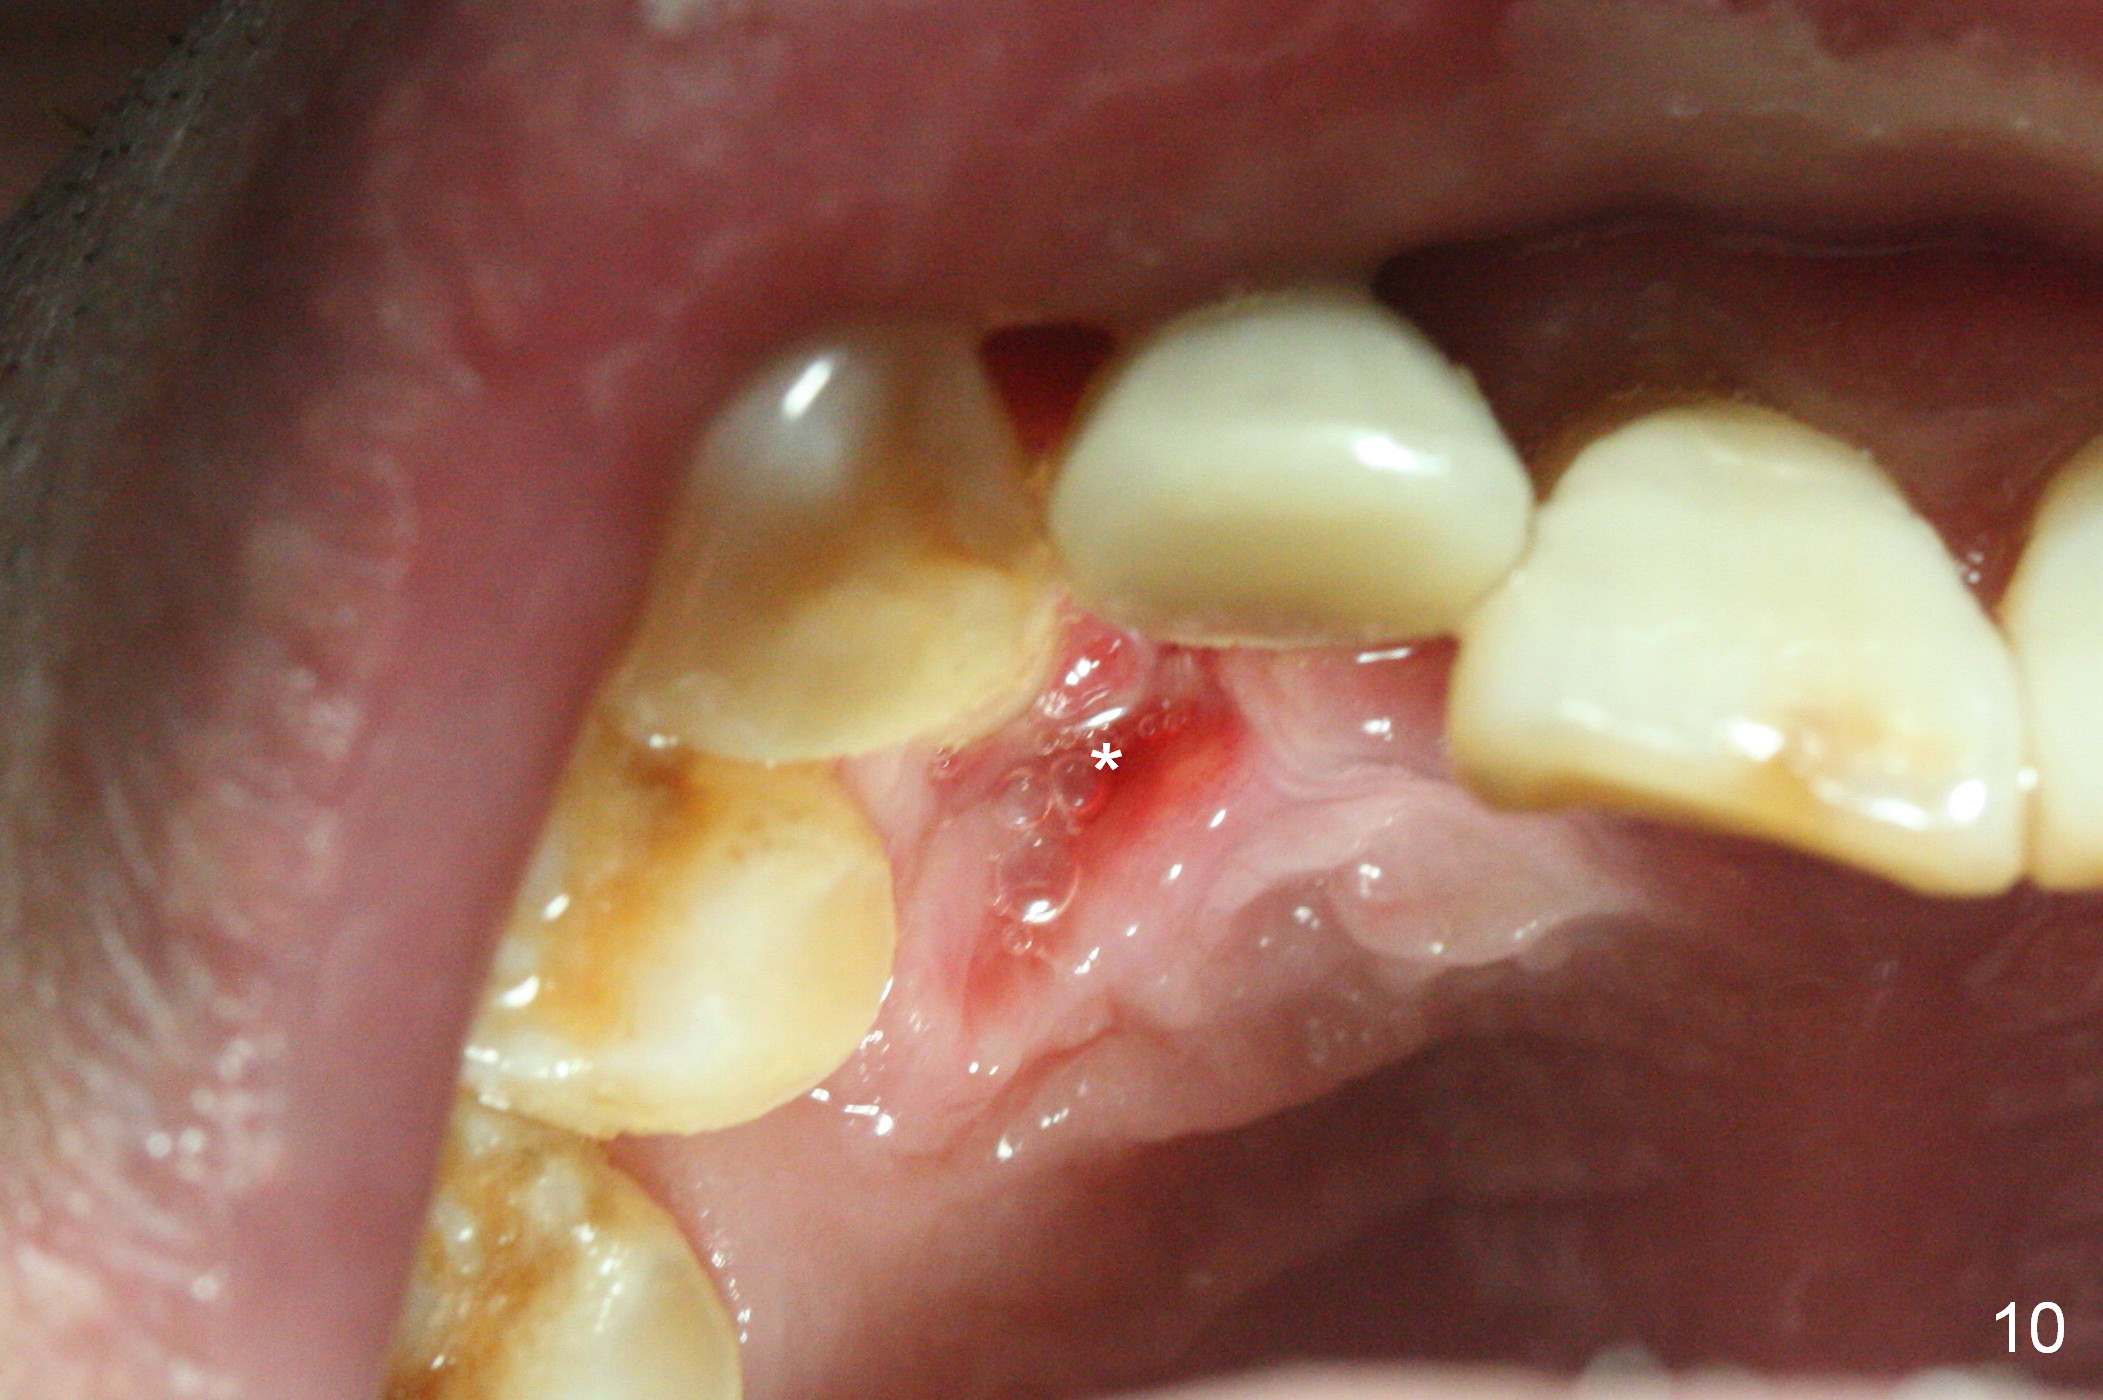

Sixteen days postop, the patient is doing fine, although the labial fistula has not disappeared (Fig.8 <). The detached distolabial papilla is healing (Fig.9 *) with mild bone graft exposure (^). The lacerated distopalatal papilla is also healing (Fig.10 *). These complications are related to flap surgery. The apical portion of the socket appears to have reduced 4 months postop (Fig.14). When the definitive restoration is delivered 5 months postop, there is gingival recession, including the distal of #8 (Fig.11 arrows, which is expected to improve over time) due to flap surgery. The labial plate collapse is minimal (Fig.12 *), while the palatal laceration (Fig.10) has healed (Fig.13). When the patient returns 1.5 years post cementation, there is increased bone density next to the coronal portion of the implant, equivalent to the bone graft (Fig.15 *). The fistula is absent (Fig.16). The crestal bone loss remains 2.5 years post cementation (Fig.17 *), although there is no sign of periimplantitis (magnification). Oral hygiene is poor. There is no change in the soft (gingival recession; data not shown) or hard tissues 3 years 8 months post cementation (Fig.18).